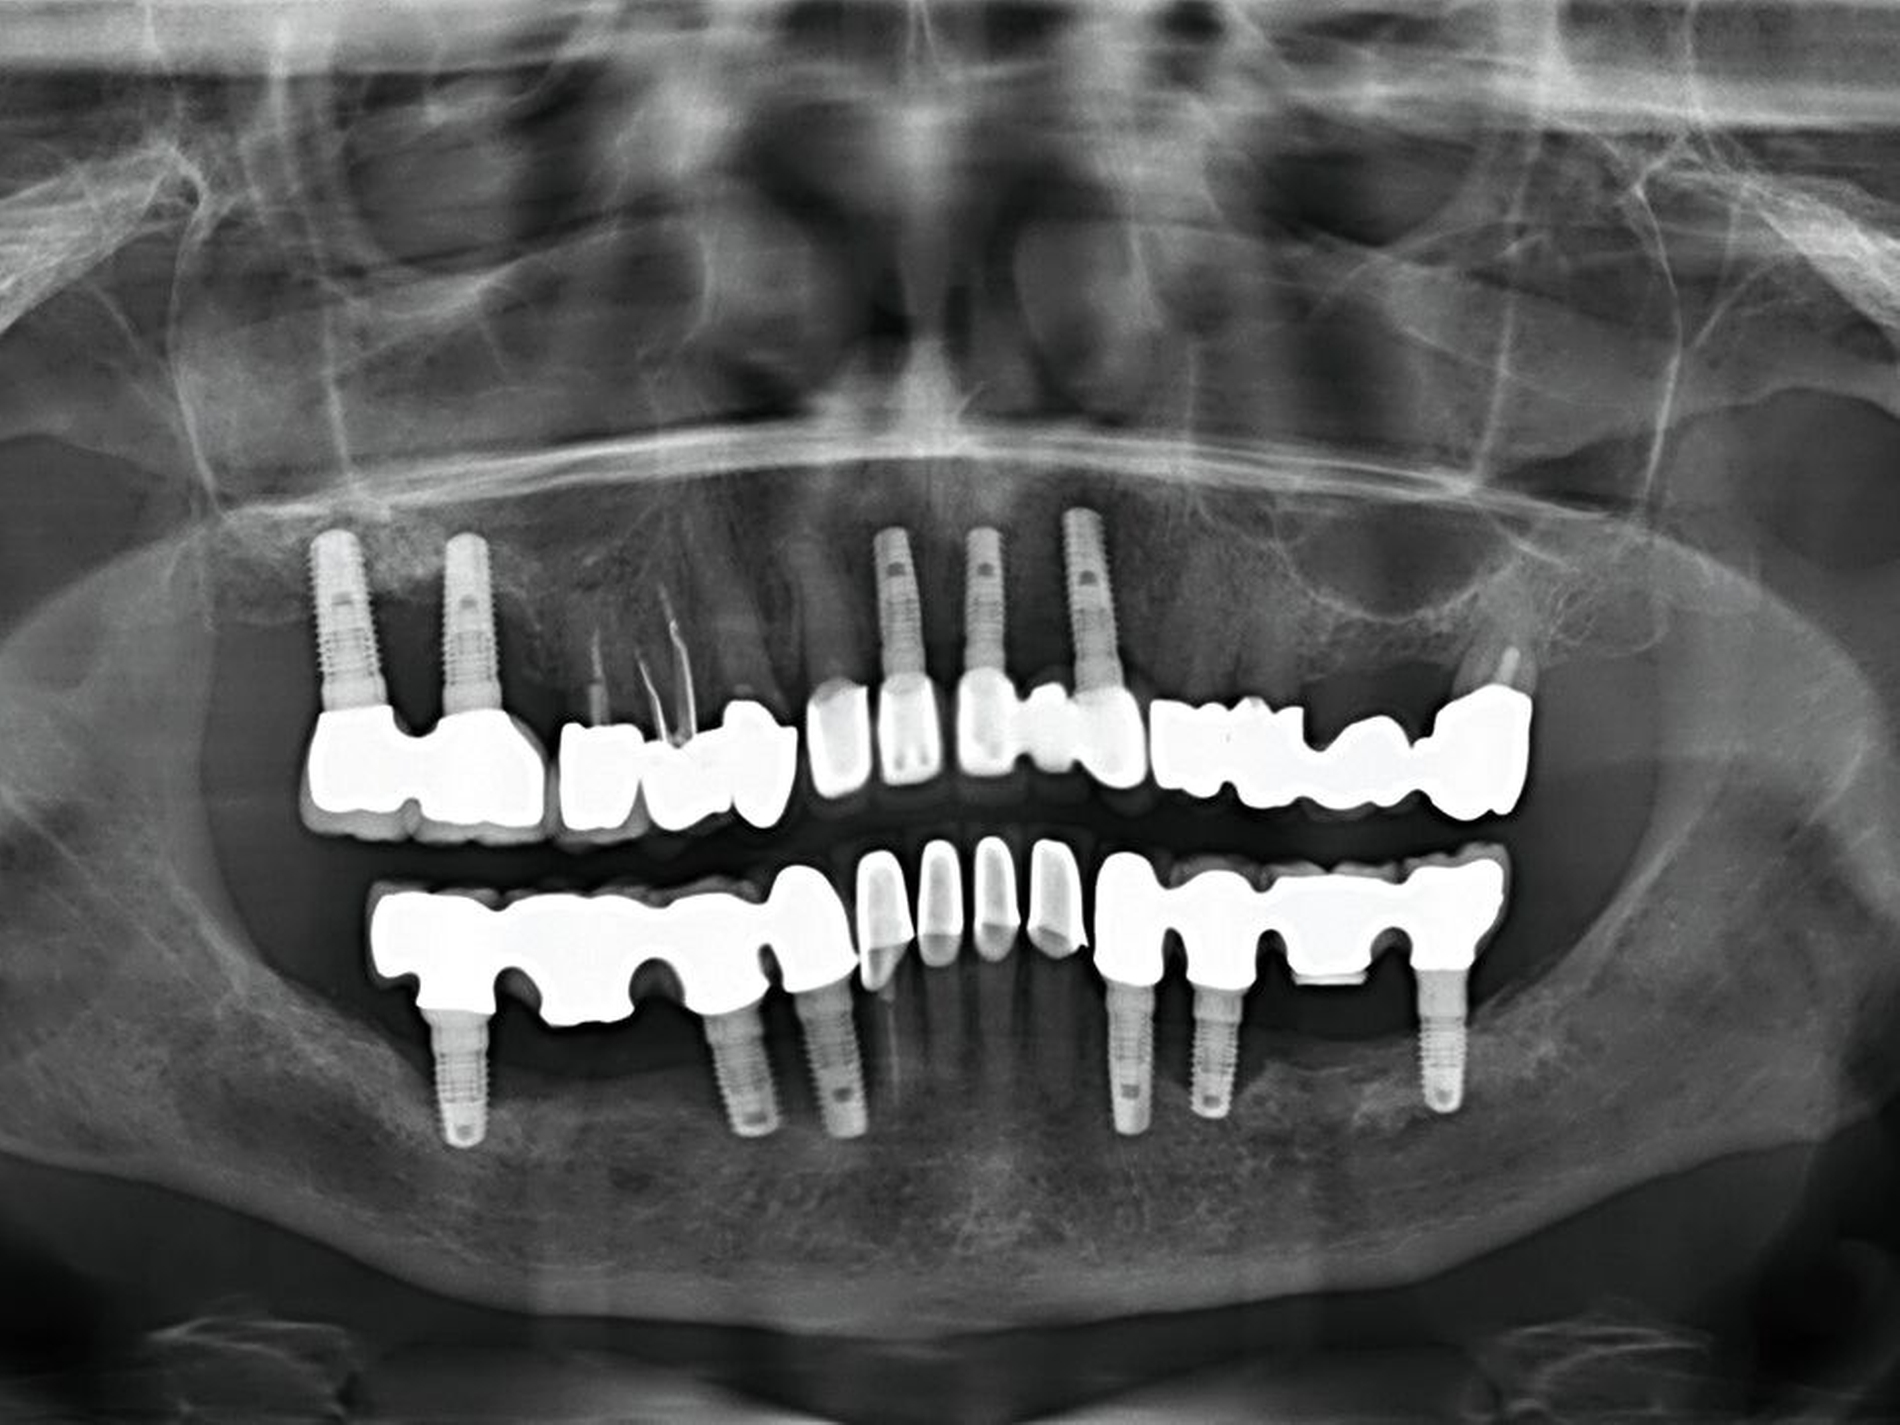

Die Versorgung einer Lücke mit Zahnimplantaten nach einem dentalen Trauma wird in der Regel nach Abschluss des pubertären Wachstumsschubes erwogen oder besser noch ins frühe Erwachsenenalter verlegt. Wenn zu diesem Zeitpunkt keine Sofortimplantation zusammen mit der Zahnwurzelextraktion erfolgt, sollte die Möglichkeit der Ridge preservation geprüft werden. Wenn eine Versorgung mit Zahnimplantaten erfolgt, dann nicht in der Akutphase des Traumas, sondern nach Abheilung der Weichteilwunden und der direkten allgemeinen Traumafolgen (Abbildung 5).

Dislokationsverletzungen von Zähnen können nicht selten mit einer Fraktur des zahntragenden Alveolarfortsatzes kombiniert sein, die auf Panoramaschichtaufnahmen oder gegebenenfalls weiterführenden Aufnahmen (Einzelzahnfilm, DVT) zur Darstellung kommen. Je nach Schweregrad wird hier zwischen einer partiellen Fraktur (Bruch der vestibulären oder oralen Alveolenwand) und einer vollständigen (Bruch der vestibulären und oralen Alveolenwand) im Sinne einer dislozierten beziehungsweise nicht dislozierten Fraktur des Alveolarfortsatzes unterschieden.